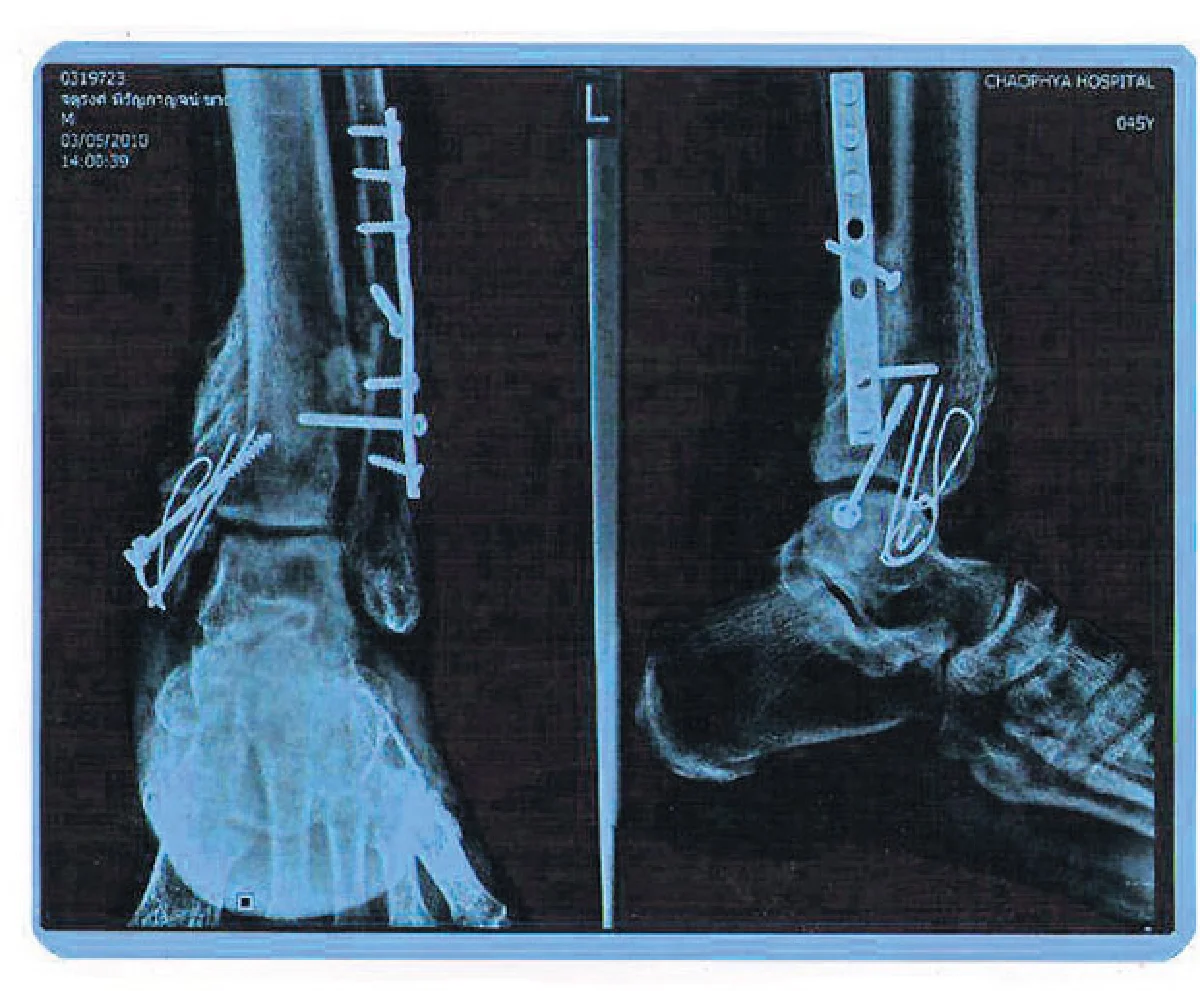

นับตั้งแต่วันที่ 27 ธ.ค. 2552 หลายวันผ่านไป ยามนี้ญาติพี่น้องยังไม่ได้ข่าวคราวของคนที่นอนเจ็บอยู่ในห้องไอซียู เจ้าตัวยังคงอยู่ในนิทรา สภาพทั้งตัวถูกพันด้วยผ้าพันแผล เพราะได้รับบาดเจ็บสาหัส ข้อเท้าทั้งสองข้างหัก ท่อนขาบนมีอาการร้าว ซี่โครงด้านซ้ายหักทิ่มเข้าที่ปอด สภาพใบหน้าบวมช้ำจนไม่เหลือเค้าหน้าเดิม และที่สำคัญสมองเขาถูกกระทบกระเทือนอย่างหนัก ชายหนุ่มที่ตอนนี้ยังไม่รู้ว่าเป็นใครมาจากไหน เข้ารับการผ่าตัดอยู่หลายครั้งหลายหน เรียกว่าสภาพไม่น่ารอด จนคุณหมอได้แต่ภาวนาให้มีปาฏิหาริย์เกิดขึ้นกับชายที่นอนนิ่งอยู่เบื้องหน้า